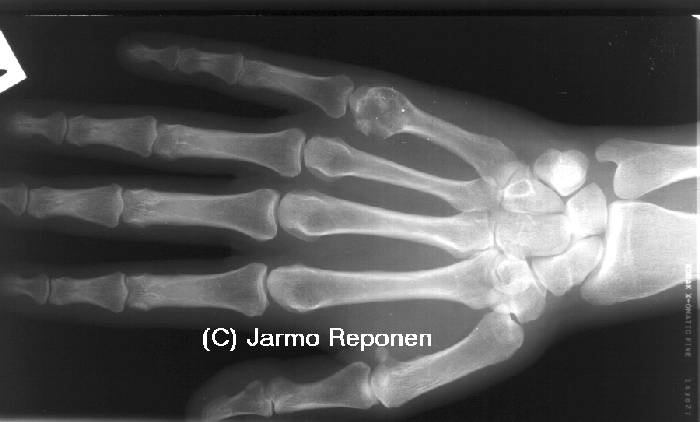

Enchondroma in the Metacarpal Bone

Enchondroma in the metacarpal bone. Enchondroma in the metacarpal bone